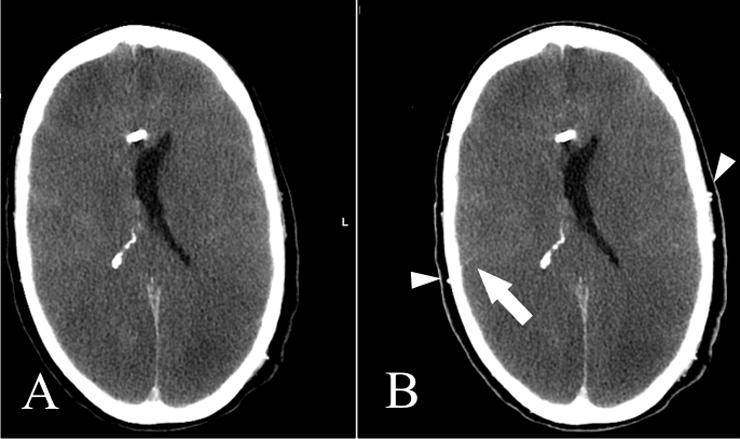

Figure 2

A: Non-contrast CT shows subarachnoid and subdural haemorrhage; gray matter/white matter differentiation is not discernible. B: CTA with contrast media in the superficial temporal artery on both sides indicating a technically sufficient study (white arrows). There is no intracranial arterial opacification. C: Venous-phase CT shows opacification of an M3 segmental artery on the right (white arrow) but no contrast in the M4 segments of the middle cerebral artery and/or the internal cerebral veins. Cerebral circulatory arrest was confirmed.